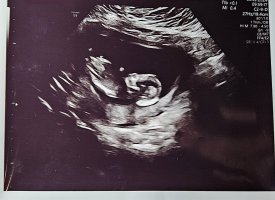

Kan legge til at bildene ble tatt da jeg var 12 + 6God kveldEr det noen som klarer å tyde kjønn fra disse bildene? Jeg synes dette er for vanskelig selv og jeg er så fryktelig spent. På forhånd takk

Er ikke ofte man ser et så bra bilde av nub, Så her ser man kjønnet godt og det er ingen tvil.

På bildet jeg legger ved ser du tydelig de to strekene på jente, mens en gutt i uke 13 ville stått opp med stacking.